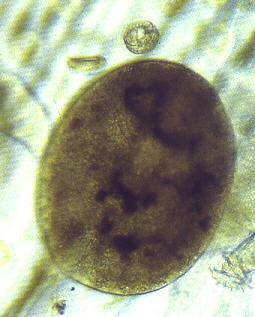

原因虫は、原生動物の繊毛動物で、学名イクチオフチリウス・ムルチフィリス(Ichthyophthirius multifiliis)という。虫の大きさは0・7㎜程度で、大きなものは1㎜を越すものもあり、多くは肉眼でも確認できる。形は卵形または球形で、体全体が繊毛で覆われ、繊毛を動かすことによって遊泳する。

白点虫は、魚の表皮を通過して表皮と真皮の境に寄生し、繊毛運動をして、血液や上皮組織の崩壊細胞を食べる。この刺激で、寄生された部位からは多量の粘液が分泌され、魚は体をこすり付けるような動作をする。

夏場の白点虫(水温20℃以上)は肉眼ではほとんど見ることができないくらい小さいので、体をこすり付けるような動作を繰り返すようなら疑ってみたほうがよい。40~100倍程度の顕微鏡で見ると、黒い球形、または卵形の白点虫を確認できる。